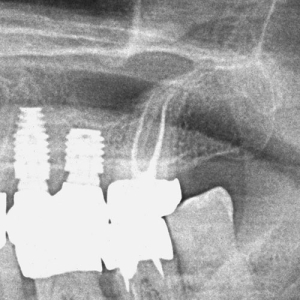

Realizarea cavității de acces în dinții cu camere pulpare calcifiate (pietre pulpare) reprezintă o provocare majoră și, în absența magnificației optice (vizualizare mărită), poate duce la pierderi semnificative de structură dentară sănătoasă. De aceea, utilizarea tehnologiei moderne de mărire de până la 25 de ori, este necesară pentru un tratament precis, sigur și minim invaziv.

Furcațiile (ramificațiile) din profunzimea canalelor reprezintă o complexitate anatomică ce poate influența designul cavității de acces, în special la dinți precum premolarii mandibulari.

Prin utilizarea microscopului dentar operator, medicul poate realiza o cavitate de acces cât mai mică posibil, care permite un control superior al procedurii și păstrarea unei cantități maxime de structură dentară sănătoasă. Astfel, tratamentul endodontic atinge un echilibru optim între eficiența mecanică și respectarea principiilor biologice, pentru rezultate predictibile și durabile.